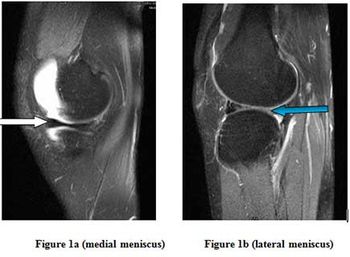

Bucket Handle Tear of Lateral Meniscus ByMadan Mohan Gupta, N.U.,Bahri, H.P. ParekhApril 15th 2014Case History: 26-year-old male with complaints of pain and swelling in left knee joint, had sustained knee injury from falling from a bicycle one month prior.